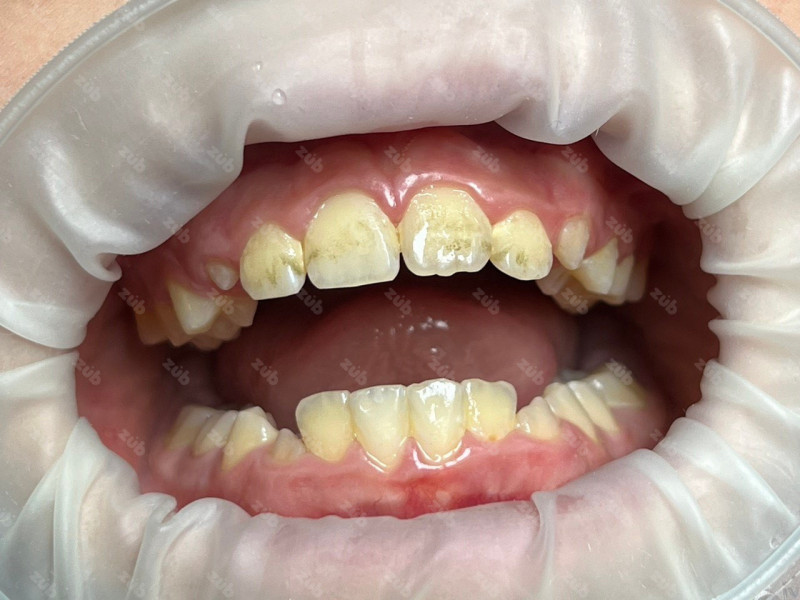

На странице представлено портфолио стоматологий Санкт-Петербурга с работами до и после профессиональной чистки зубов. В нашем портфолио собраны разные клинические случаи: от удаления незначительного налета до снятия массивного поддесневого камня. Здесь вы можете увидеть, как возвращается естественный цвет и внешний вид зубов после процедуры. Изучите результаты до и после чистки зубов, чтобы увидеть реальный эффект и выбрать клинику в Санкт-Петербурге, где профессиональная гигиена поможет вернуть зубам здоровый вид.

Стоматология ЗУБ (ZUB)

Профгигиена